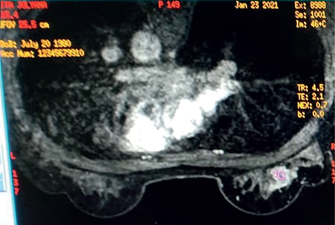

Post-Treatment UWBI

Post-operative findings on US are similar to mammogram and MRI, although the current recommendation of NCCN does not mention UWBI-based imaging as essential in this stage (Figure 4) (7). Seroma, hematoma, and lymphedema are commonly depicted as anechoic fluid collections. Solid to cystic nodules can be observed as well, and some of these may be resorbed completely as the healing process occur. The occurrence of lymphedema should raise an awareness for possible delayed breast cellulitis, as seen among patients who had surgery in upper lateral segment of the breast. Skin thickening findings are benign, and usually appear as bright echogenic lines with hypoechoic dermis (63, 67, 68). Fat necrosis appears as a solid hypoechoic mass mostly with posterior acoustic shadow since it is a complex of intra-cystic or solid masses. While cystic masses possess internal echogenic bands, which is highly influenced by the patients’ current position, solid masses have circumscribed or ill-defined margins due to alterations of breast parenchyma area (69).

Fig 4

Figure 4. Imaging algorithm of breast imaging in pre-treatment phase of management as adapted from NCCN 2022 guidelines. Abbreviation: ALP, alkaline phosphatase; LFT, liver function test (70).